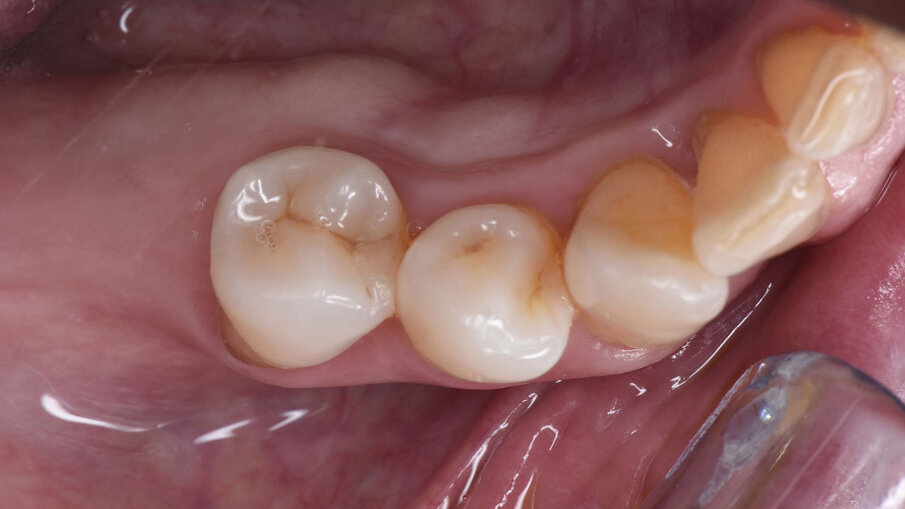

Dopo due settimane, è stata eseguita una scansione 3D con scan body e sono state consegnate due corone provvisorie avvitate sugli impianti, in modo da poter condizionare i tessuti molli peri-implantari (Figg. 11-12b). A causa di un’inadeguata banda di mucosa cheratinizzata sul versante vestibolare, è stato eseguito un intervento di vestiboloplastica con affondamento di fornice e innesto epitelio-connettivale prelevato dal palato (Figg. 13, 14). Dopo un’ulteriore maturazione dei tessuti, una nuova scansione ha permesso di dare informazioni all’odontotecnico circa il tragitto transmucoso ottenuto con i provvisori e sono state consegnate due corone definitive avvitate in zirconio (odt. Alessandro Giacometti; Figg. 15-19b). La paziente è stata seguita con controlli periodici clinici e radiografici a 6 mesi, 1 anno e 2 anni dal carico protesico (Figg. 20a, 20b).

Figg. 19a, 19b_Immagine clinica e radiografica che mostrano il manufatto protesico finale.

Figg. 20a, 20b_Controllo clinico e radiografico a due anni dal carico protesico.